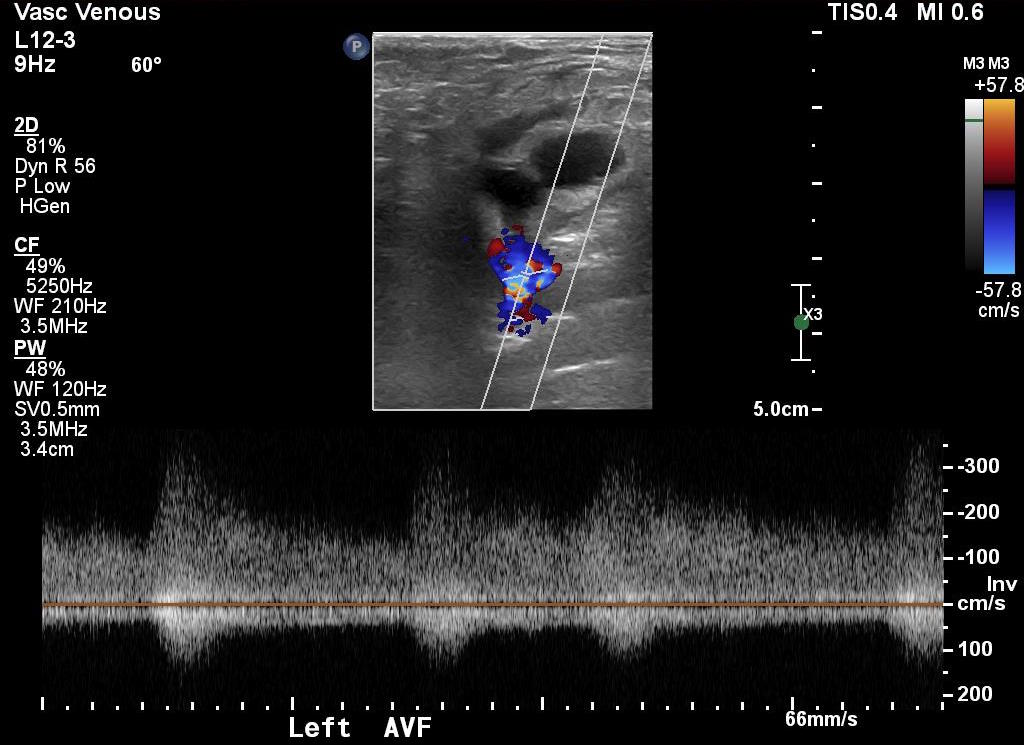

The patient is a middle aged man who after an interventional procedure was referred to my clinic with an expanding hematoma due to a pseudoaneurysm complicated by an arteriovenous fistula. He was a week out from his procedure and had grown a hematoma roughly the size of a hard boiled egg in his left groin which caused him pain. A duplex scan showed a pseudoaneurysm (below) with fistula flow.

preduplex12

On examination, he had this well circumscribed indurated hematoma of hard boiled egg size with tenderness. There was a bruit on auscultation. Duplex showed a small chamber of flow adjacent to the proximal superficial femoral artery emptying into the femoral vein. Doppler in the common femoral vein showed relatively high fistula flow, and this is reported to be associated with failure of thrombin injection. CTA (top) demonstrated flow of contrast from femoral artery to vein through a pseudoaneurysm chamber that laid between. Angulation to an axial orientation showed this better (below).

The procedure went as planned. Ultrasound guided access is aided with dual live display of B-mode and color flow (below)

Arteriography showed much of the contrast from injection of the pseudoaneurysm to preferentially go to the artery which made me worry less about creating a DVT/PE. With balloon inflated (below), thrombin was injected and balloon inflation held for about 30 seconds.